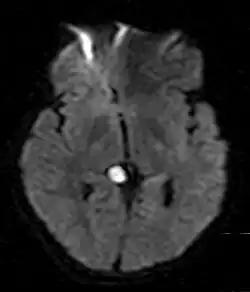

Im Gehirn tritt die Epidermoidzyste als gelappte, unregelmäßige, blumenkohlartige Raumforderung auf. Ihre Dichte ähnelt liquorähnlicher Flüssigkeit, welche keine Kontrastmittelanreicherung aufweist. In der Magnetresonanztomographie ist sie vor allem dadurch zu unterscheiden, dass sie in der Flair-Sequenz nicht vollständig signalsupprimiert ist, d. h., es besteht eine Hyperintensität im Vergleich zu Liquor. In 10 bis 25 % der Fälle sind Verkalkungen vorhanden. Am häufigsten finden sich Epidermoidzysten im Kleinhirnbrückenwinkel (75 %) und im 4. Hirnventrikel (20 %). Sie entstehen beim Embryo aus Einschlüssen an der Oberfläche der Haut während des Neuralrohrverschlusses.